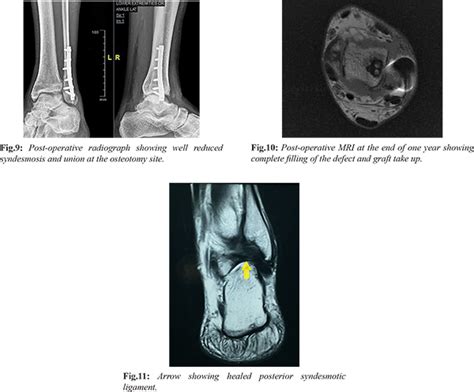

Mosaicplasty by a Modified Lateral Malleolus Osteotomy Approach for ...